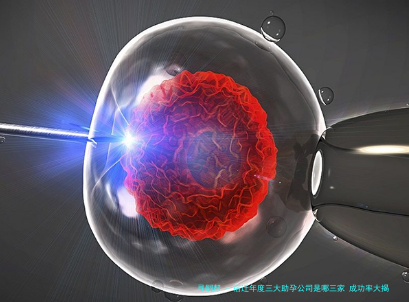

| C机构 | 科研创新,技术前沿 | 基因筛查、 *** 等新型方案 | 信息缺失(以技术创新吸引客户) | 注重科学研究与技术创新 | 信息缺失 |

| D机构(公立) | 公立三甲,资源整合,中西医结合 | 三代试管(PGS技术)、胚胎基因筛查 | 约50%(高龄女性及反复流产患者中表现突出) | 个性化治疗方案,全程心理辅导和营养支持,中西医结合调理 | 3-5万元 |

| E机构(公立) | 综合性公立医院,多学科协作 | 三代试管(全基因组测序) | 约45% | 开设中西医结合调理门诊 | 3-5万元 |